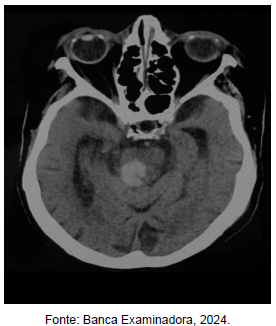

Com base na figura acima, em qual região do tronco cerebral está localizada a hemorragia?